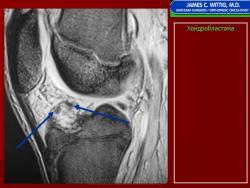

Хондробластома — это редкая доброкачественная опухоль, локализующаяся, главным образом, в эпифизе и отличающаяся своеобразным клеточным составом. Ткань новообразования представлена овальными, округлыми и веретеновидными клетками, напоминающими незрелые хондроциты (хондробласты). Зрелый гиалиновый хрящ определяется лишь в некоторых опухолях. Возраст больных варьирует. Мужчины поражаются в два раза чаше женщин. Пациенты предъявляют жалобы на боли в течение нескольких месяцев или лет, у некоторых больных определяются внутрисуставной выпот, припухлость и ограничение движений. Наиболее типичная локализация опухоли — проксимальные эпифизы плечевой и большеберцовой костей, а также дистальный эпифиз бедренной кости. У 20 % больных опухоль развивается в плоских или коротких трубчатых костях, преимущественно в пяточной и таранной. Изредка поражаются кости лицевого черепа, в том числе височная. В большинстве случаев новообразование выходит за пределы эпифиза и распространяется на метафиз. На фоне остеолиза обнаруживаются рассеянные участки обызвествления в виде пунктирных линий, а также разреженный трабекулярный рисунок. Хондробластома, как правило, не выходит за пределы кости, но изредка проникает в полость сустава. В процессе роста опухоли иногда возникает вторичная аневризматическая костная киста.

Рентгенологически хондробластома представляет собой сравнительно большой (2-4 см) очаг округлой формы, четко отграниченный от окружающей кости склеротической каймой. На фоне очага в большинстве случаев, но не обязательно определяются плотные включения, напоминающие хлопья ваты.